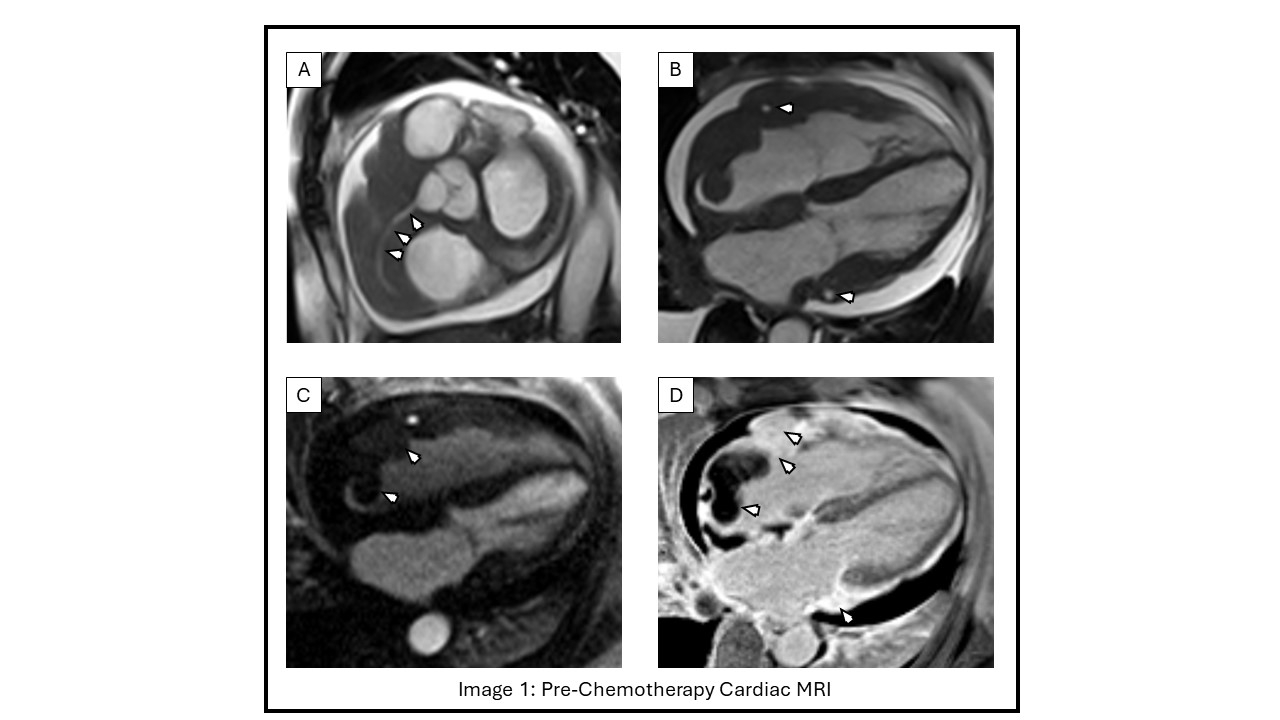

We present a case illustrating clinical outcome of a patient treated with Polatuzumab plus standard Rituximab, Vincristine and Prednisone (Pola-R-CHP) for metastatic DLBCL with profound cardiac involvement. She is a 56-year-old female who presented with pre-syncope associated with night sweats, myalgia and weight loss. On examination, a grade II/VI tricuspid regurgitation murmur was auscultated. CT showed chronic right lower lobe pulmonary embolism along with axillary and mediastinal lymphadenopathy. New findings of a mass protruding into the right atrium with thickening of right atrial and ventricular walls, a right atrial thrombus and small pericardial effusion were reported. Cardiac MRI characterized the mass to be partially vascularized with extension from right to left chambers encasing RCA and coronary sinus with diffuse interstitial expansion and inflammation (Image 1). Axillary lymph node biopsy was consistent with aggressive B cell lymphoma with positive CD19, CD20 and BCL2 markers. Hospital course was significant for polymorphic VT with degeneration into VFib arrest. ROSC was achieved after one round of ACLS. Multiple factors may have contributed to VT including myocardial inflammation, possible tumor induced RCA compression and prolonged QT. Amiodarone and anticoagulation were initiated and patient was discharged with a wearable cardiac defibrillator along with oncology and cardio-oncology referrals.